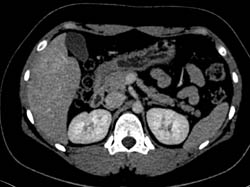

Hepatic Adenoma